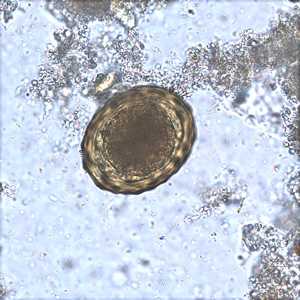

February - 2008 - Case #221

A survey was conducted to determine the prevalence of geohelminth infections in school-age children living in Haiti. The laboratory aspect of the survey consisted of processing stool specimens which were collected in 10% formalin.